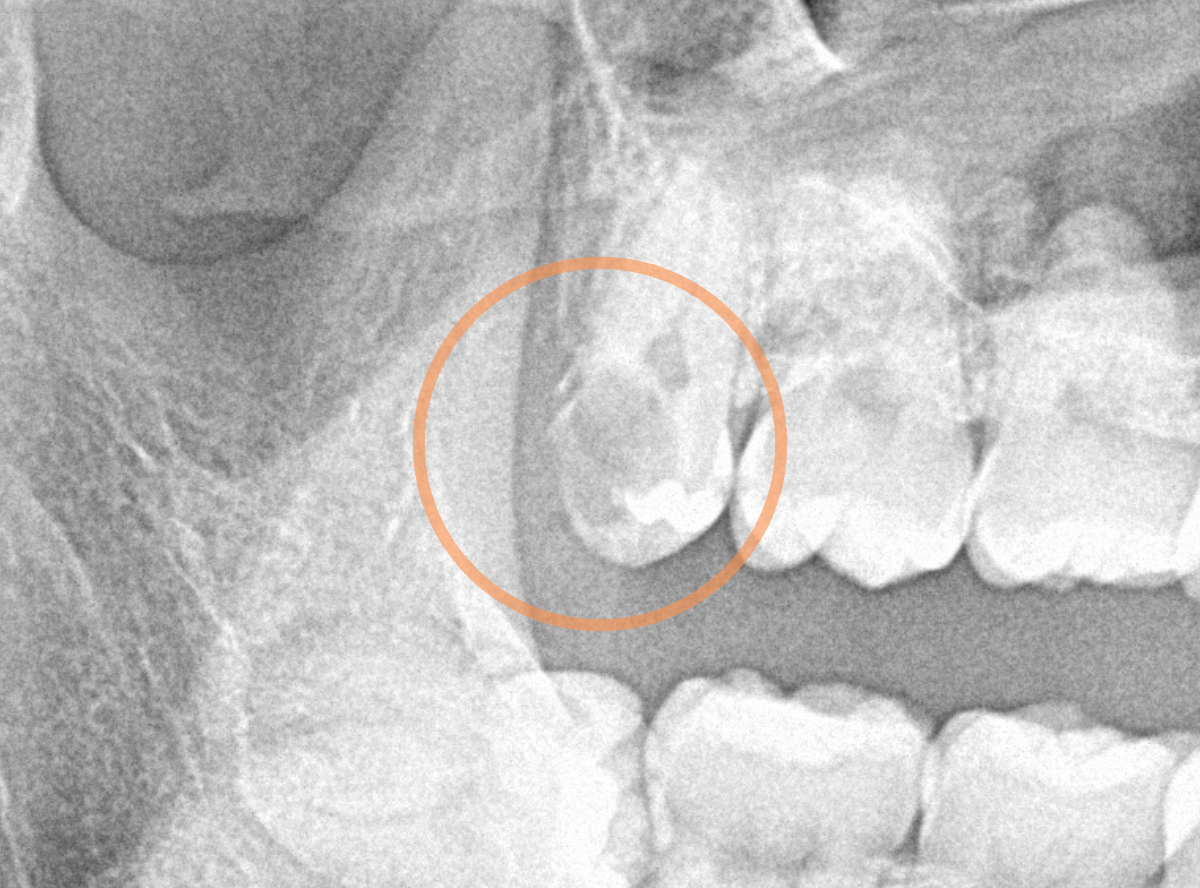

抜歯後に長期間お痛みが出たり、経過観察が必要な難しいおやしらずの抜歯ならまだしも、簡単なおやしらずの抜歯を避けてしまったがために、他の歯に悪影響を与えてしまったもったいない例も多々見てきました。

ここでは、比較的簡単なおやしらずの抜歯の例を中心にご紹介します。

このようなおやしらず、あなたはありませんか?